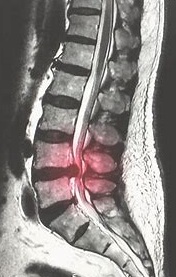

Bel ağrıları geniş yayılmış və polietiolojikdir, yəni yaranma səbəbləri çox müxtəlifdir.

Bu səbəblər arasında ən çox rastlanan degenerasiyadır (onurğa biləşənlərinin yıpranması).